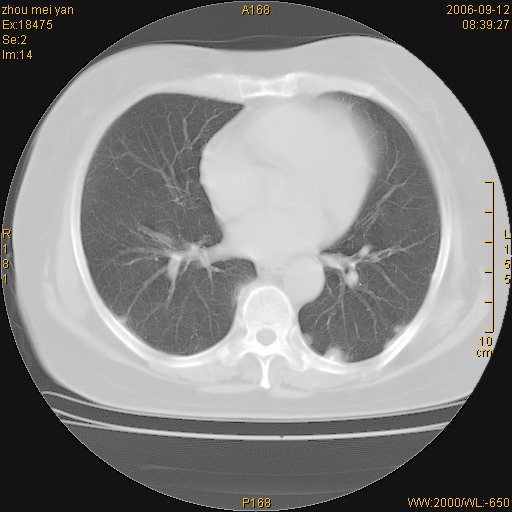

患者、女、55岁。因心率失常住院检查ct发现胸部多发结节。腹部b超肝、胆、胰、脾、肾、子宫附件未见异常。无结核病史,无粉尘接触史。请大家来会诊。谢谢!

病变位于胸膜,多发结节,边界清楚,内见小结节状钙化。其它未见异常。

双侧胸膜多发结节,形态不规则,边缘较清楚,每一个结节中心似乎都有钙化点的特征,与胸膜广基相切。临床无结核病史,无粉尘接触史。

影像表现十分有特点:双侧肋胸膜及膈胸膜广泛散在分布大小在2至6mm左右,较大病灶中心可见钙化。

双侧肋胸膜及膈胸膜广泛散在分布大小不等结节影,较大病灶中心可见钙化。